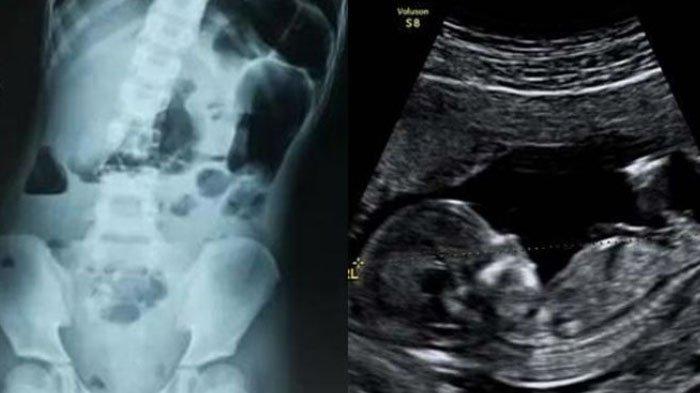

Dokter di awal menduga adanya tumor di indung sel telurnya.

Wan Wensheng dari Departemen Bedah Kardioraks, mengatakan bahwa selama operasi ada teratoma kitik berdiameter 10 kali lebih besar dari ovarium.

Tumor lahir di ovarium kiri gadis itu volumenya 10 kali lebih besar dari ovarium menyebabkan teratoma terbalik, dan ovarium muncur.

Setelah ditelusuri secara mendalam oleh pihak dokter, fakta mencengangkan justru ditemukan.

Mengejutkan adalah ketika ternyata tumor itu sebenarnya adalah calon jabang bayi.

Embrio yang bersembunyi di dalam perutnya.